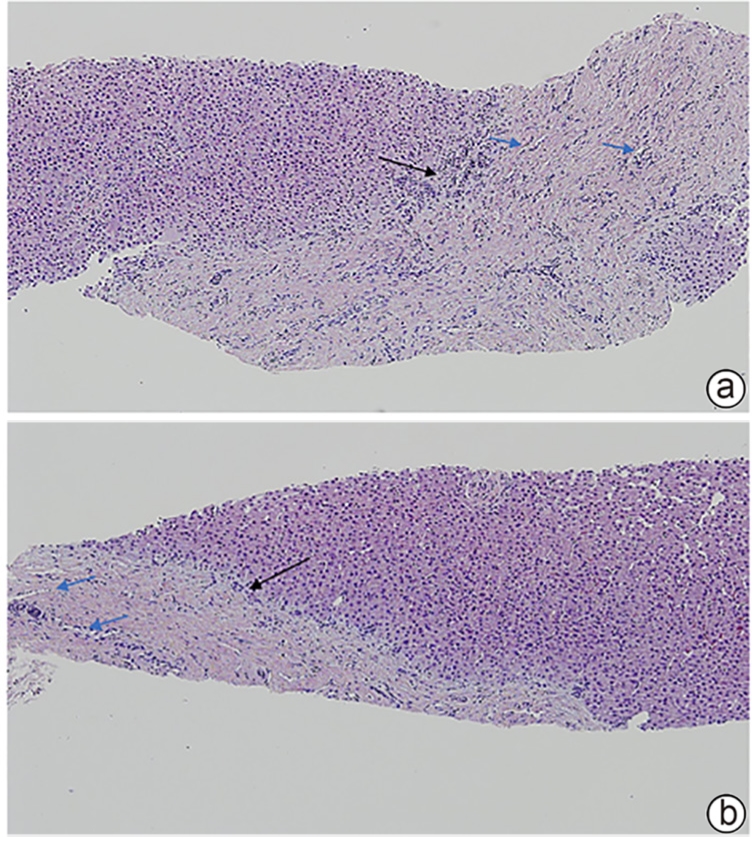

Expression profiles of HBsAg and HBcAg in liver tissue and their correlation with serological markers in children with chronic hepatitis B

Yue JIANG, Lina JIANG, Shuhong LIU, Bokang ZHAO, Junqi NIU, Jingmin ZHAO

2025, 41(10): 2037-2043. DOI: 10.12449/JCH251013

Abstract:

Objective  To investigate the expression features of HBsAg and HBcAg in liver tissue and their correlation with HBV serum markers in children with chronic hepatitis B (CHB).  Methods  A total of 257 patients who were consecutively admitted to The Fifth Medical Center of Chinese PLA General Hospital from January 2013 to December 2023 and underwent liver biopsy to achieve a confirmed diagnosis of CHB were enrolled in this study. The NIS-Elements system was used to capture the immunohistochemical images of HBsAg and HBcAg in liver tissues, and Image J software was used for quantitative analysis. The one-sample chi-square test was used for within-group comparison of continuous data, and the Pearson/Spearman/Kendall’s Tau-b correlation analysis was used to investigate the correlation between viral antigen expression and serological markers.  Results  Among the 257 CHB patients, there were 162 children (76 children aged<5 years and 86 children aged 5 — 18 years) and 95 adults. There were significant differences in the expression pattern, area, and intensity of HBsAg and the area and intensity of HBcAg in liver tissue between different age groups and between the children with different HBeAg statuses (all P<0.05). In the children aged<5 years, HBsAg staining area was significantly negatively correlated with anti-HBs and HBeAg (both P<0.05)and was significantly positively correlated with ALT and AST (both P<0.05), and HBsAg staining intensity was significantly positively correlated with qHBsAg (P<0.05) and was significantly negatively correlated with anti-HBs (P<0.05). In the children group, HBsAg staining area was negatively correlated with anti-HBs and HBeAg (both P<0.05), and HBsAg staining intensity was positively correlated with qHBsAg (P<0.05) and was negatively correlated with anti-HBs (P<0.05). In the adult group, HBsAg staining area was positively correlated with ALT, AST, and liver inflammatory activity (all P<0.05), and HBsAg staining intensity was positively correlated with qHBsAg, HBeAg, and HBV DNA (all P<0.05) and was negatively correlated with liver inflammatory activity and fibrosis degree (both P<0.05). In the children aged<5 years, HBcAg staining area was positively correlated with qHBsAg and HBV DNA (both P<0.05), and HBcAg staining intensity was significantly positively correlated with HBV DNA (P<0.001). In the children aged 5 — 18 years, the area and intensity of HBcAg staining were positively correlated with qHBsAg, HBeAg, and HBV DNA (all P<0.05). In the children group, HBcAg staining area was positively correlated with qHBsAg, HBeAg, and HBV DNA (all P<0.05), and HBcAg staining intensity was positively correlated with qHBsAg and HBV DNA (both P<0.05). In the adult group, the area and intensity of HBcAg staining were positively correlated with qHBsAg, HBeAg, and HBV DNA (all P<0.001), and HBcAg staining area was positively correlated with the serum level of ALT (P=0.043).  Conclusion  The expression levels of HBsAg and HBcAg in liver tissue of children with CHB are significantly correlated with serological markers, and in clinical practice, HBsAg and HBcAg combined with serological markers can help to assess the condition of the liver, determine the immune stage, and provide evidence-based guidance for treatment timing.